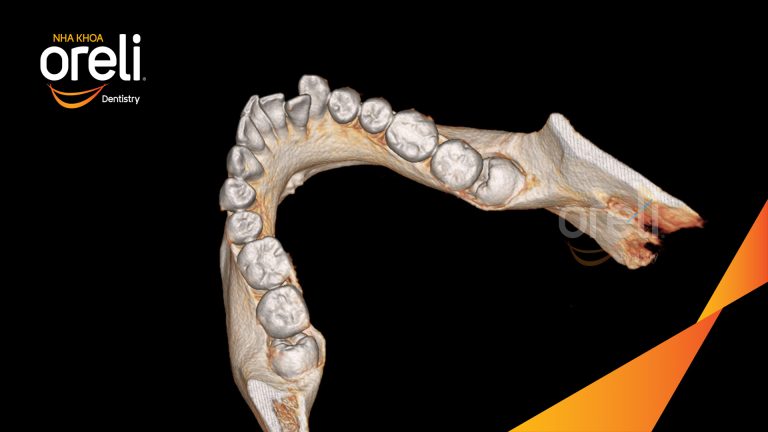

Nhổ răng khôn hàm dưới – Case tại Oreli Buôn Ma Thuột

Nhổ răng khôn

Mọc lệch